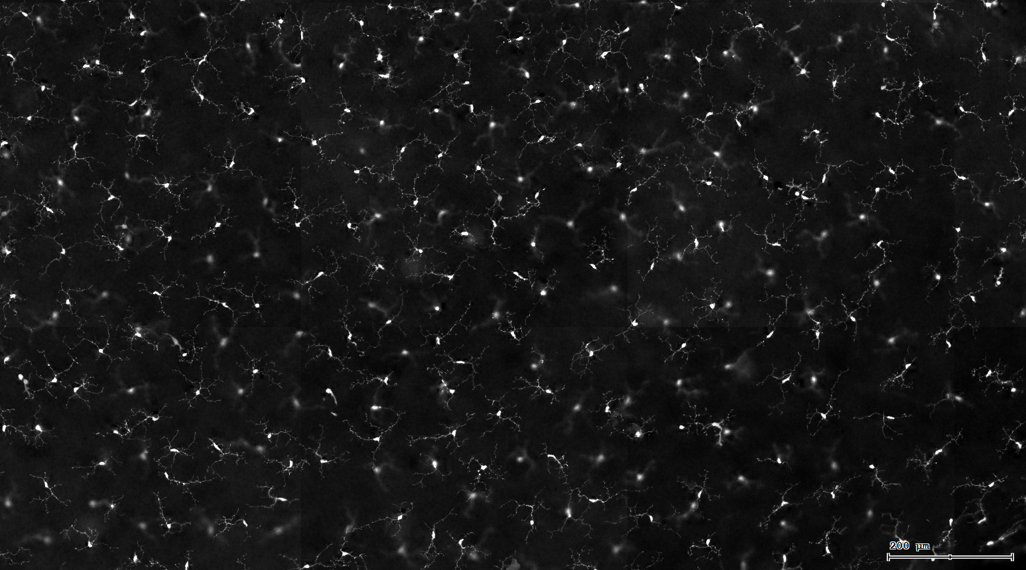

3. 根据FITC通道识别神经胞体并筛选出有效细胞胞体(细胞核识别算法)。

根据染色强度,染色面积,细胞形态学,利用正反向回溯功能和设门圈选Gating,排除杂质,细胞碎片,黏连细胞(绿色框线标记),获得有效的神经元胞体,(粉色框线标记),并将胞体按照面积分为两类(散点图)。

由于该视网膜样本是标记的小胶质细胞,根据面积将神经胞体分为两类(Small bodycell,Big bodycell),反向回溯Big bodycell中的细胞后,应用Input Gate功能筛选短粗的神经纤维,作为激活态的小胶质细胞。

激活态小胶质细胞识别